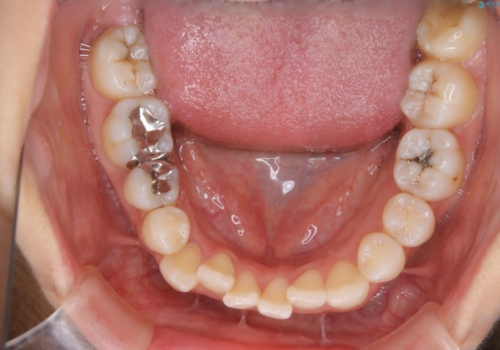

- 矯正装置

- ワイヤー矯正 審美装置

- 治療計画

- 歯のガタつき、顎のズレ、出っ歯を気にして来院された患者様です。

歯を抜きたくないとの希望であったためマウスピース治療をお勧めしましたが、

マウスピースをずっとつけていることは難しいとの事であったためワイヤー矯正治療を行うこととなりました。